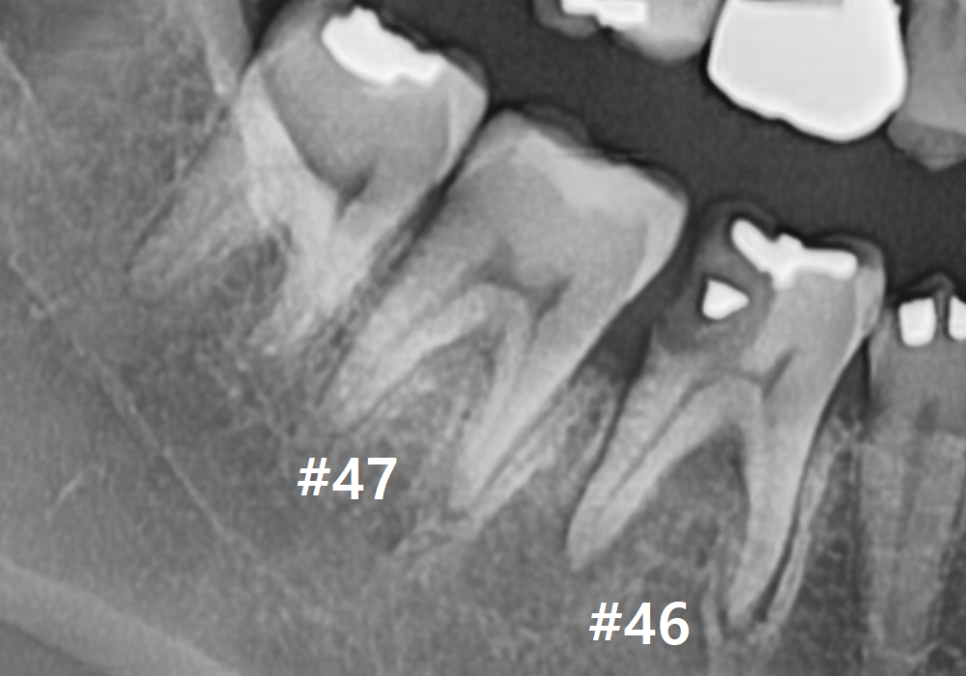

빨간색으로 표시한 부분이

주요 신경인 '하치조 신경'인데,

거의 맞닿아 있을 정도로

염증이 많이 퍼져있는 게 보이시나요?

안타깝지만, #46 치아는

서둘러 발치를 진행해야 했습니다.

여기에 더해 바로 뒤쪽 어금니(#47)의

옆면까지 충치가 전이되어 함께 썩고 있었는데요.